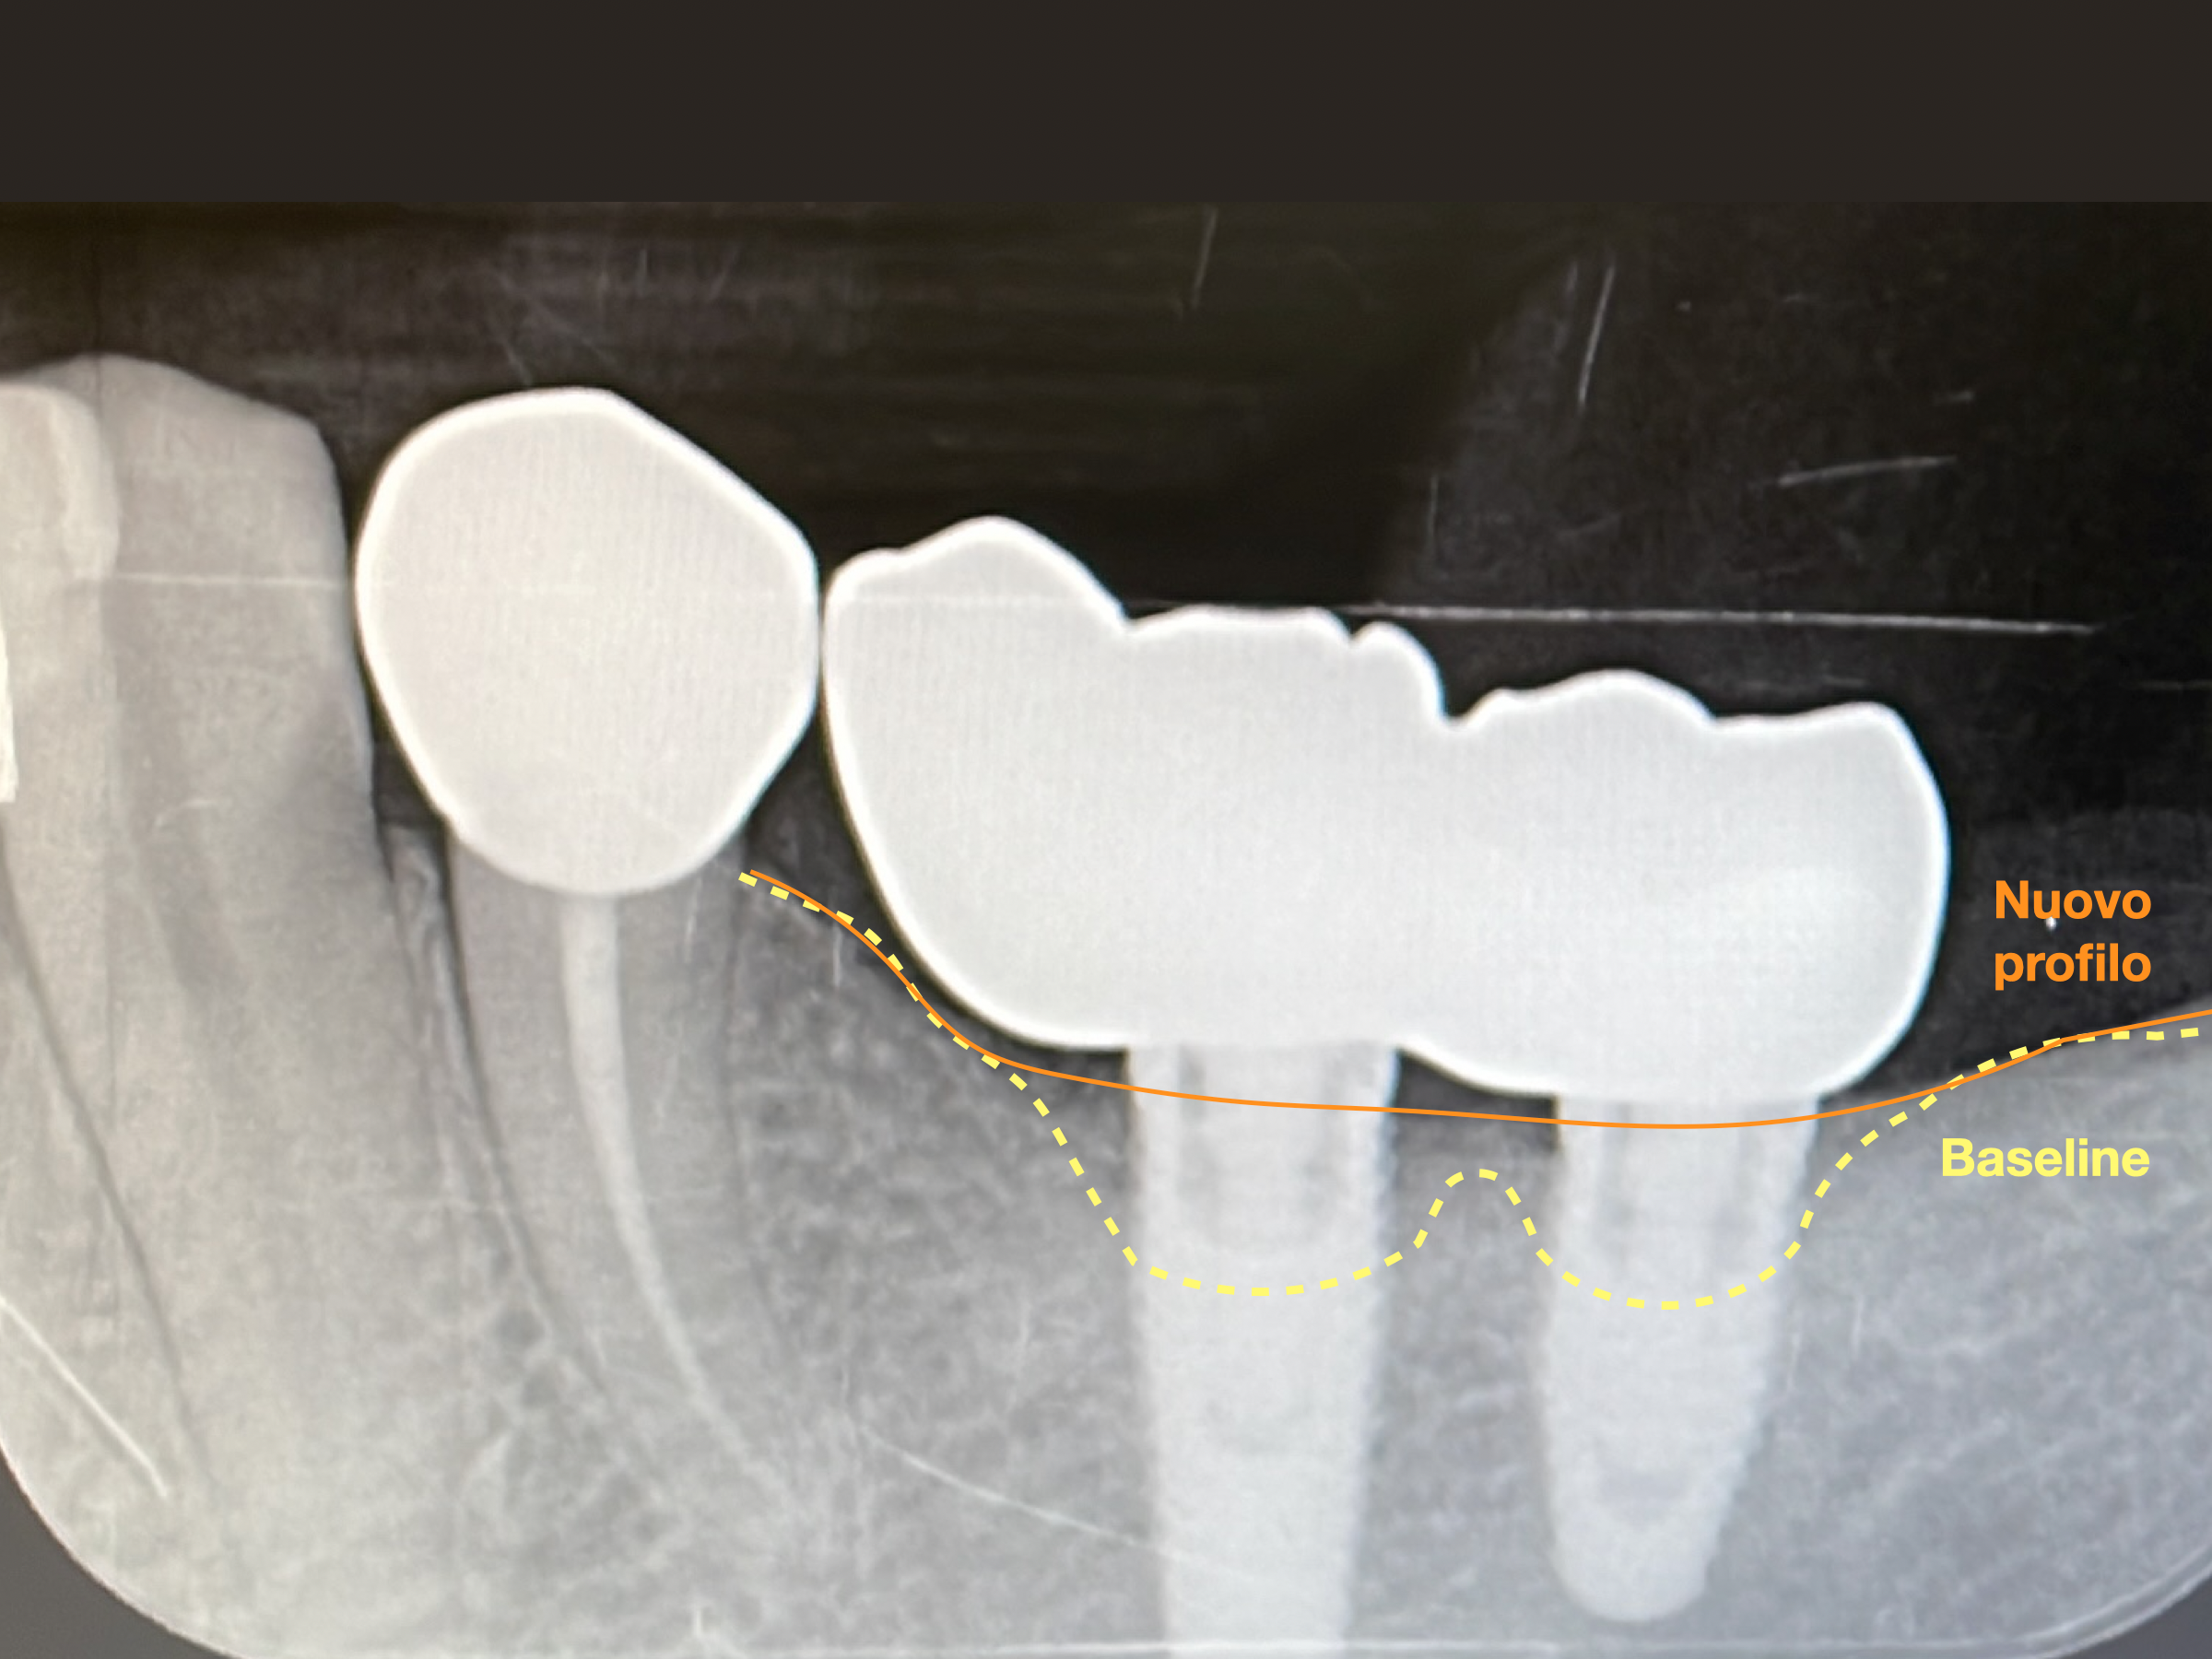

Nel caso clinico che presentiamo, è stata eseguita una GBR (Guided Bone Regeneration), rigenerazione ossea guidata:

📸 Radiografie e foto mostrano chiaramente il recupero del supporto osseo e la stabilità dell’impianto a distanza di mesi.